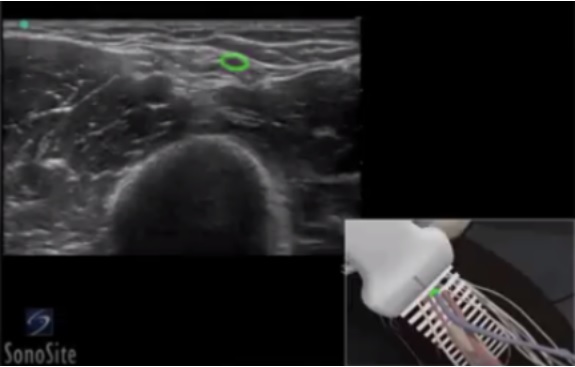

Peripheral IV (PIV) Basilic Vein Image